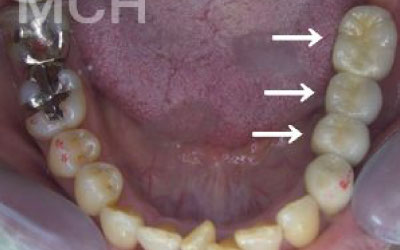

2 歯が傾いてくる、落ちてくる

歯は互いに支え合ってバランスを保っています。つまり、歯が抜けるとその支えがなくなり、抜けた部分の隣の歯が倒れたり、上の歯が下に沈んだりすることがあります。